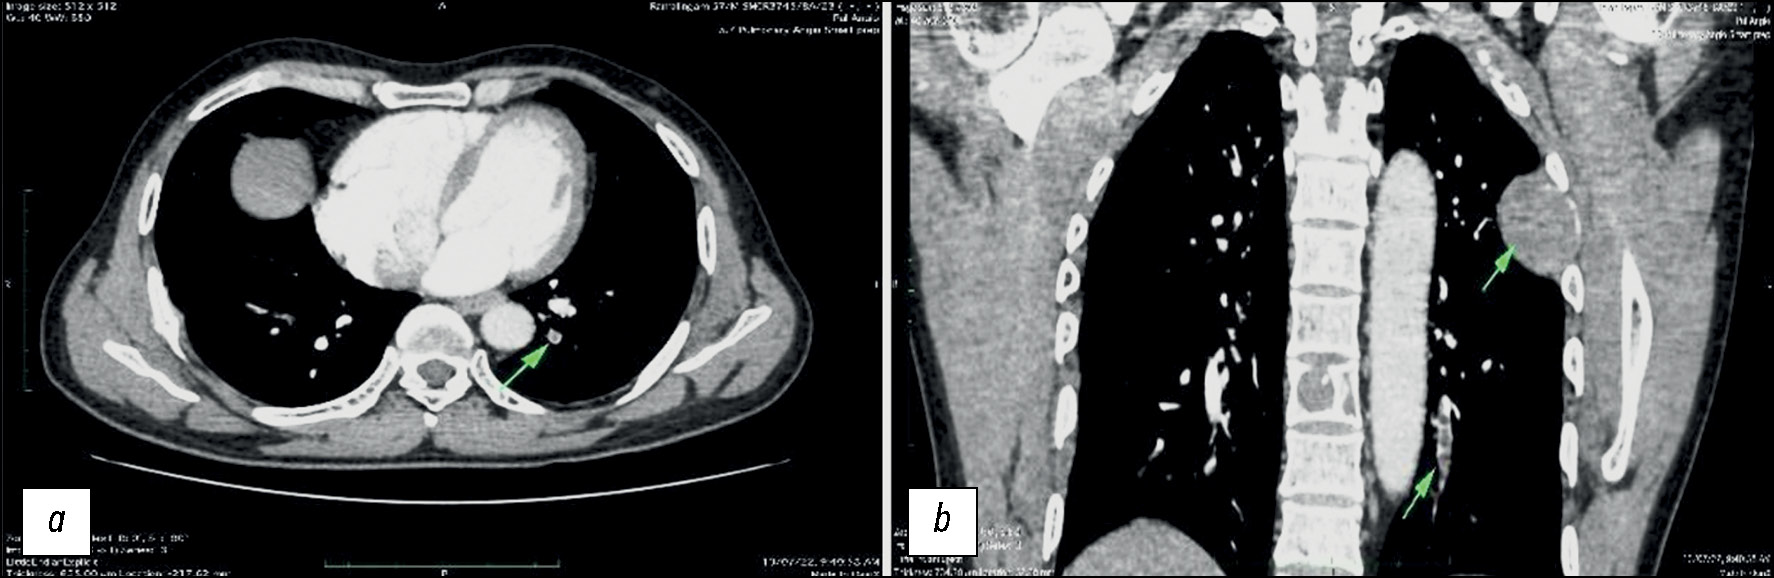

Несколько наглядных случаев изменений сосудов лёгких и кишечника у пациентов с COVID-19 показаны на рис. 1–3.

Рис. 2. Результаты компьютерной томографии, выполненной у пациента мужского пола, 33 лет, с COVID-19: a — тромб в заднем сегменте нижней доли левого лёгкого; b — плотное поражение мягких тканей в левом лёгком, прорастающее в область прилежащего ребра, и очаг деструкции в грудном позвонке.

Рис. 3. Результаты компьютерной томографии брюшной полости с контрастированием, выполненной у пациента мужского пола, 34 лет, с COVID-19: a — уплотнение жировой ткани сальника в правой нижней части живота, что свидетельствует о наличии инфаркта сальника; b — утолщение стенки подвздошной кишки в области дистального отдела с гипоконтрастированием по сравнению с прилегающей кишкой.